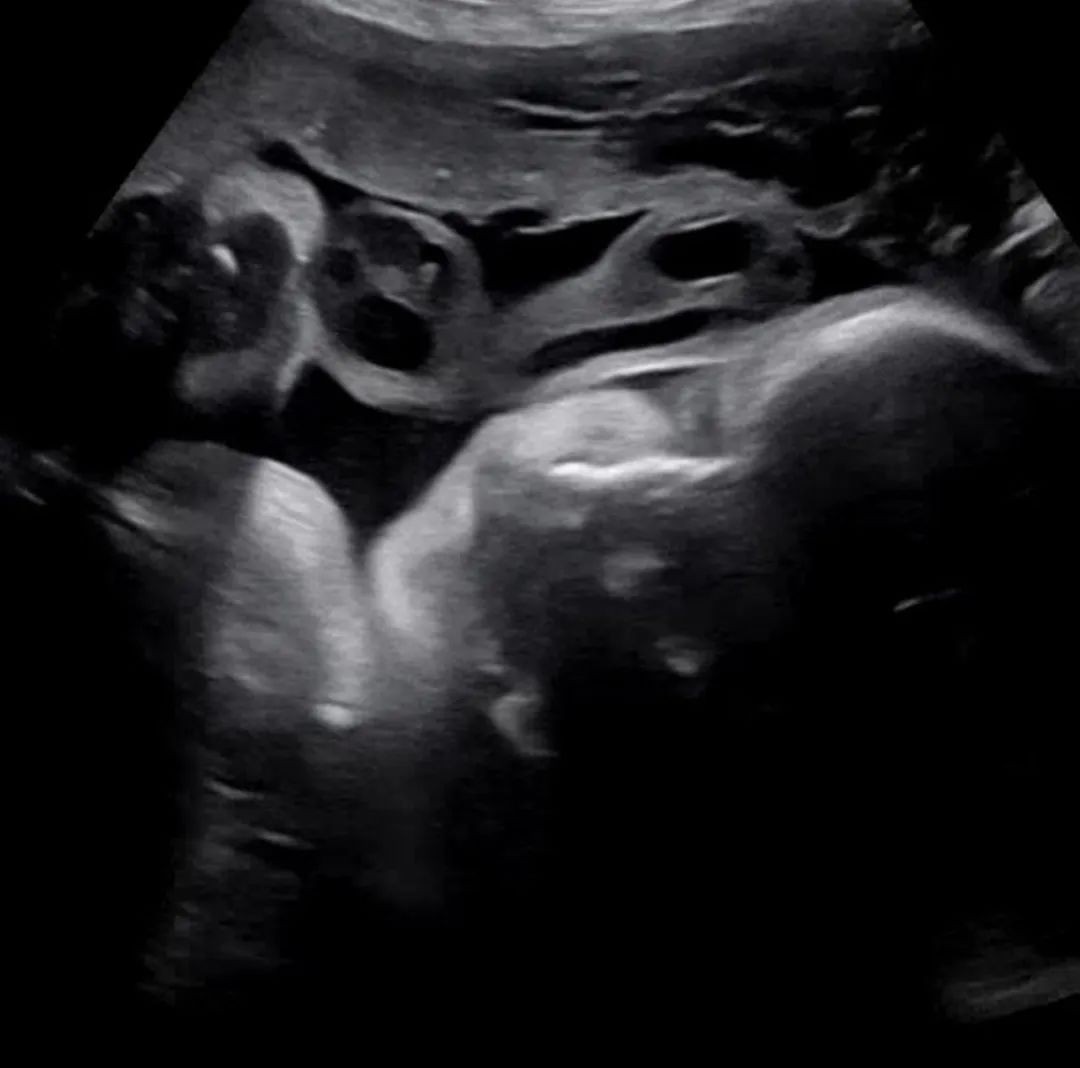

这期间两人一直都在ins上与大家分享怀孕期间的近况,收到了很多人的支持与鼓励。眼看9月初就快到朴诗恩分娩的日子,然而这时又传来了噩耗,让众人都感到非常吃惊和遗憾。

而且陈泰贤还将ins头像改为了胎儿B超的黑白照,同时个性签名中的“死产”一词也非常引人注目,可以感受到他的内心十分难受。